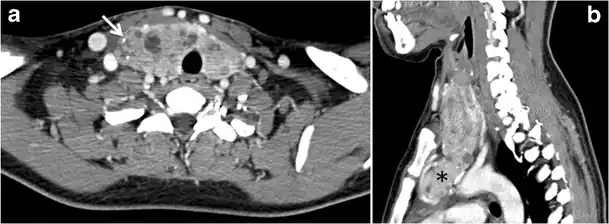

Fig. 13. A 27-year-old female patient known to have goiter. a, b Axial and sagittal enhanced CT scan images of the neck demonstrate a heterogeneously enhancing, enlarged thyroid gland with scattered calcifications (white arrow), cystic changes, and substantial retro-sternal extension (black asterisks). No lymphadenopathy or substantial airway narrowing.[1] -

Malignancy can coexist within the goiter and a CT scan may give a clue if there are abnormal cervical lymph nodes and/or signs of invasion. Retrosternal extension (Fig. 15) could affect the surgical approach, as a lower extent may require a partial or total sternotomy to facilitate complete resection. Therefore, the distance of the retrosternal extent from the sternal notch should be measured on a sagittal image.[1]

A goiter is an abnormal thyroid gland proliferation that manifests as multi-nodular, uni-nodular, or non-nodular diffuse glandular enlargement. A goiter is formed of solid matrix, colloid cysts, blood products, calcification, and fibrosis, and this heterogeneity may lead to variable appearances on a CT scan (Figs. 13, 1414 and and15)15). The US is more sensitive in evaluating thyroid nodules within a goiter; however, a symptomatic goiter may require surgical treatment with total thyroidectomy, and in this case CT plays an additional role in preoperative evaluation. Specific aspects for examination on a CT scan during the preoperative evaluation for goiter include extension, mass effect, and suspicious features of malignancy.[1]